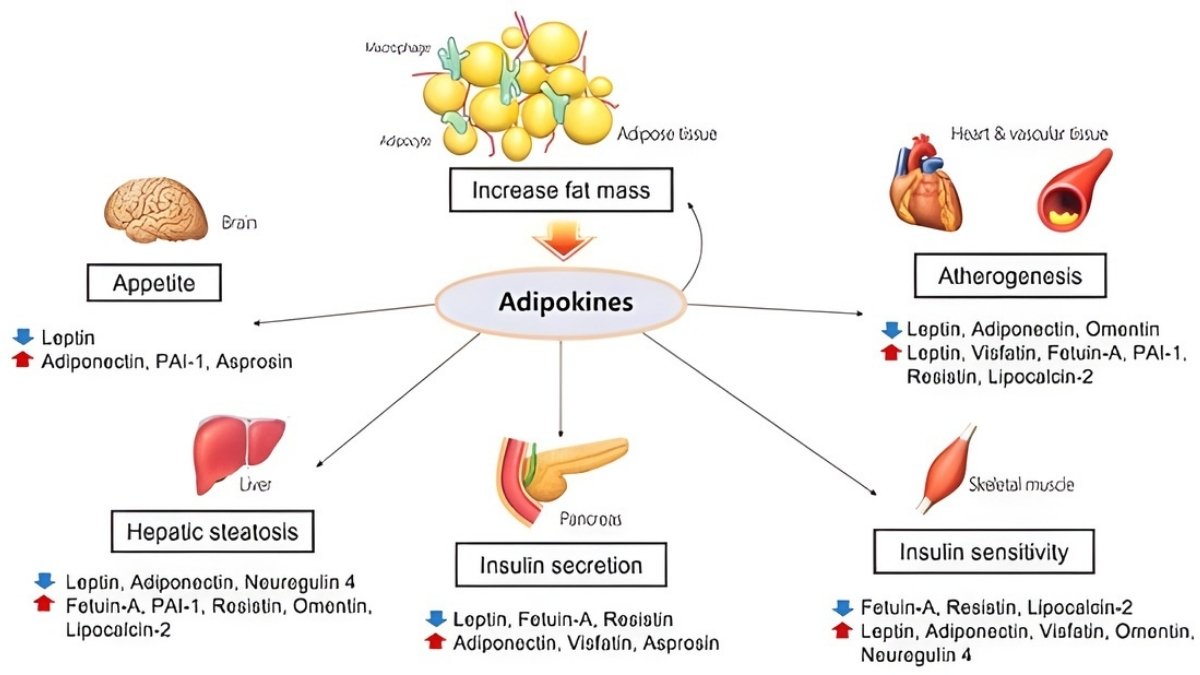

Adipokines: The Inflammatory Molecules Destroying Your Joints

Your fat tissue isn’t just storage. It’s an active organ pumping out hormones called adipokines. These molecules travel through your blood to your joints. And they cause serious damage.

The main players are leptin, adiponectin, resistin, and visfatin. Studies show adipokine levels are “distinctly higher” in OA patients compared to healthy people. These molecules predict cartilage loss on MRI scans.

Higher leptin levels mean higher chances of needing knee replacement surgery. Synovial fluid—the liquid in your joints—shows adipokine levels that directly match pain severity.

Leptin: The Pain Amplifier

Leptin is a 16-kDa protein your fat cells make. More body fat means more leptin. This molecule stimulates IL-6, IL-8, and TNF-α in your joint tissues. These are inflammatory signals that cause pain and swelling.

Leptin hits cartilage cells directly. It triggers pathways that break down the cushioning matrix. Women typically have higher leptin levels than men. This partly explains why women get OA more often. The more you weigh, the more leptin you make. And the more your joints suffer.

Adiponectin: The Paradox Molecule

Adiponectin seems helpful at first. At low levels, it reduces inflammation. But in OA, something changes. The joint environment turns adiponectin from friend to enemy.

In arthritic joints, adiponectin increases MMP-1 and MMP-3 production. These enzymes chew up cartilage. Research shows adiponectin correlates with aggrecan degradation—that’s the main cushioning protein in your joints breaking apart. Higher adiponectin doesn’t protect you. It makes things worse.

The Cumulative Effect

Multiple adipokines work together. They create both local joint inflammation and whole-body inflammation. The infrapatellar fat pad—a fat deposit in your knee—pumps adipokines directly into the joint space.

This explains why both weight-bearing joints (knees, hips) and non-weight-bearing joints (hands, wrists) get damaged. It’s not about pressure. It’s about metabolic signals traveling through your bloodstream. Your hand arthritis and knee pain share the same root cause.